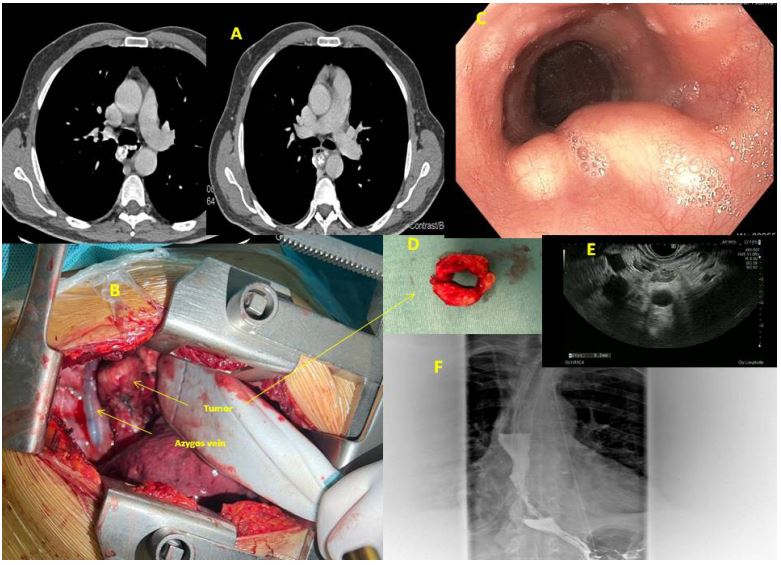

Figure 1: (A) CT pre-operative image of the leiomyoma; (B) Intraoperative image of the tumor; (C) Endoscopic view; (D) Donut-like leiomyoma; (E) EBUS image; (F) gastriographin swallow control after surgery.

A 61-year-old man, heavy smoker with cirrhosis Child-Pugh a alcohol associated, was admitted for surgery. The lesion had a donut-like shape and arised from the muscular layer of the midesophagus. The patient was studied with CT scan, Endoscopy and EBUS with biopsy and with PET scan showing a SUVmax = 1,9 [2]. Because of the poor functional value of spirometry and DLCO, we preferred a fast mono-pulmonary ventilation, so we choosed right lateral muscle-sparing thoracotomy of about 12 cm. The other reason to perform an open surgical access, was the cirrhosis: we were very afraid that a smallest hole in esophageal mucosa could have constituted a high risk of fistula with catastrophic outcome. So we performed a very careful myotomy and enucleoresection of the leomyoma with very great attention to separate the tumor from the mucosa which was very tiny and fragile because of tumoral growth, consistency and weight. The tumor was entirely enulceoresected and the mucosa remained intact [3]. During the hospitalization, we had to control him 3 times every day, with great attention to hepatic function, especially coagulative blood tests and albumin and protein serum levels. Nevertheless, the drainage was removed in eighth post-operative day, when the out-put was <300 ml. We began to reefed the patients after 5 days, previous gastrographin swallow and blu/methylene test. The patient was discharged after 9 days, he was very good with free diet.

We present here a case of 61 year old man, heavy smoker with hepatic cirrhosis Child-Pugh A alcohol associated. Patient underwent endoscopy and chest CT scan beacause of severe dysphagia and cough. The diagnosis was mid-esopahgeal leiomyoma. We performed a complete enucleoresection of leiomyoma of the midesophagus with direct reconstruction of the muscular wall of the esophagus. This leiomyoma was shaped such as Donut-like (Figure 1). The patient was discharged after 9 days and he was very good with free diet.